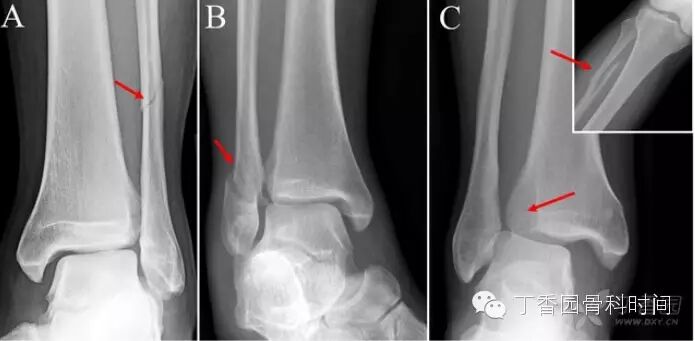

下胫腓联合韧带损伤的机制通常是踝关节外旋和过度背屈。可以导致下胫腓联合损伤的运动包括运动(足球等),低能量创伤等。外旋损伤通常发生于踝关节旋前或旋后位。胫腓联合韧带损伤可以单发或者合并骨折。典型的骨折类型包括旋前外旋型,旋后外旋型及腓骨近端骨折合并胫腓联合损伤(图3)。

图3:胫腓联合损伤合并踝关节损伤的典型X片表现。A,旋前外旋型或者Weber C型骨折,B,旋后外旋型或者Weber B型骨折,C,Maisonneuve骨折,小图示腓骨近端骨折